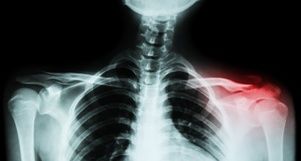

The collarbone is comprised of two elongated bones that connect the upper part of the breastbone to the shoulder blade. Because of the location of a person’s shoulder in relation to objects in a motor vehicle, it is likely to be injured a collision. Reasons that this is such a common injury include:

Symptoms of a broken collarbone include swelling, tenderness, bruising, and pain that increases with movement of the shoulder. Immobilization of the shoulder is an important aspect of treatment, which means that you will need to be off work while you recover from your injuries. Some of the treatments you may need include:

- Surgery to realign the broken clavicle and to install plates, screws, or rods to help hold the bones in place

While some people make a full recovery, you could suffer complications from a clavicle fracture. You may develop an infection after surgery or the fracture may not fully heal, which could leave you with a permanent lump in the bone. In addition, the fractured bones could cause injuries to nearby blood vessels or nerves or increase the risk that you will develop arthritis in the joint.